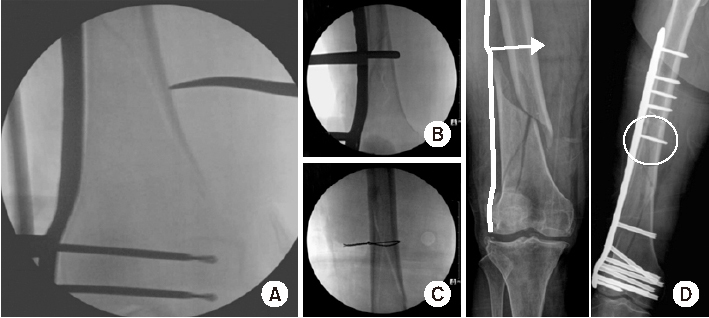

Fig. 2

Direct reduction methods in the coronal plane in distal femur fractures using a long hemostatic tonsil (A), Collinear reduction clamp (B), percutaneous wiring (C), or conventional cortical screw (D).